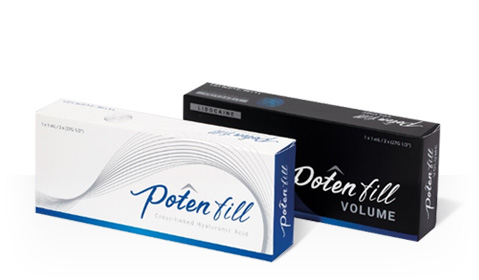

포텐필

- 특 - 징

- 미국 FDA의 원료의약품목록(DMF) 등재 및

유럽의약품 품질위원회(EDQM)의

인증을 받은 고품질 히알루론산 필러로

임상시험에서 안정성을 확인하였으며

시술 후 이상반응 발현율이 낮은 것으로

평가될 정도로 안정적인 효과를 가진 필러